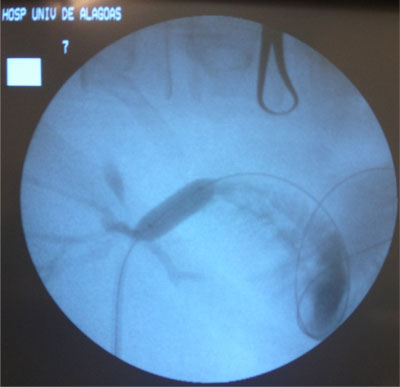

- Drenagem da Via Biliar e Dilatação da Estenose;

Dilatação com balão

- Balões maiores -> utilizados para a estenose do ducto biliar comum;

- Anastomoses biliares entéricas -> dilatação com um balão maior (10 a 20 mm de diâmetro);

Dilatação deve ser lenta e progressiva

- Evitar laceração do ducto biliar;

- Evitar sangramento no sistema biliar -> estenose fibrótica;

O tipo da estenose é importante na definição da resposta do dilatação.

Estenoses de anastomose X Estenoses não anastomótica

Estenose recorrente após dilatação de estenose biliar benigna pode ocorrer em 29-58% dos casos;

Para evitar esta complicação -> pode ser necessário “stent”. Uso do stent após a dilatação é controverso -> sucesso a longo prazo x pode estimular reação inflamatória, fibrose e formação de cálculos;